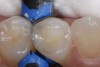

Figure 5. A bulk fill composite (Beautifil Bulk Fill Restorative: Shofu) is used to complete the occlusal aspect of the restoration.

Figure 5

Figure 6. An occlusal view of the completed distal occlusal composite restoration on tooth number 5.

Figure 6